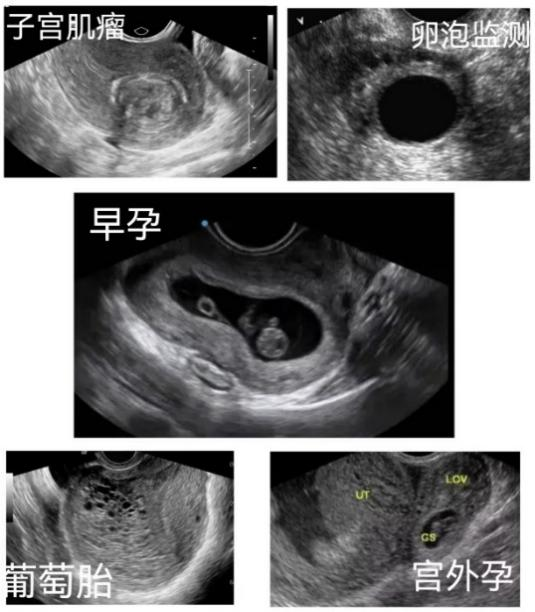

1、确定孕囊的位置及数目,明确是宫内妊娠还是宫外妊娠,辅助判断宫外孕及子宫瘢痕妊娠等异常妊娠情况。在早期发现异位妊娠方面,阴道B超优于腹部B超。

2、核实孕周、判断胚胎发育情况。根据孕囊大小及形态、胎芽长度、有无胎心、有无囊周积液等指标判断孕龄、核实孕周,辅助判断是否有胚胎发育异常,如:胚胎停育、自然流产等。

3、阴道超声在非孕期的临床应用也有很多,如:卵泡监测,子宫肌瘤、宫腔病变(子宫内膜息肉等),滋养细胞肿瘤(葡萄胎等),盆腔肿块(卵巢囊肿等),子宫畸形等等。